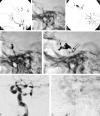

F<sc>ig</sc> 2.

Fig 2.

Eighty-seven-year-old woman (case 4, Table 1) presented with progressive ophthalmoplegia, decreased visual acuity, and chemosis. Angiogram shows a CCF with bilateral mixed dural artery supply both via the external and internal carotid arteries (type D, ref. 2), congestion of both cavernous segments with retrograde flow in both SOV. A transvenous embolization was carried out by using n-BCA with complete CCF obliteration and cure of symptoms. AD, Early- and late-phase right lateral and frontal ICA angiograms show slow contrast filling (A, thin double arrow) through dural branches of the ICA (A, arrow) including capsular arteries of McConnell at the floor of sella turcica. Retrograde filling of the SOV (arrowhead) with origin stenosis (B and C, double arrows). Note delayed contrast washout (BD, arrows) of the CS bilaterally. E and F, Frontal and lateral radiographs show the microcatheter in the left cavernous segment (arrow) before n-BCA infusion. Microcatheter was navigated through the SOV (double arrow) and the anterior intercavernous connection (arrowhead). G and H, Frontal and lateral radiograph show the n-BCA-Ethiodol cast within the CS bilaterally. Some embolic material spillage is seen in the right proximal SOV through the stenotic segment (arrow). Note the radiolucent structures within the glue cast represent the internal carotid arteries. IL, Left lateral early and late phase ICA angiograms (I and J) and right and left frontal angiogram show CCF obliteration. Note artifacts related to the embolic material (arrows).